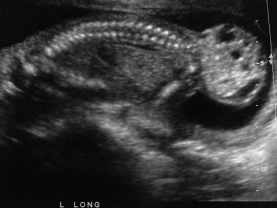

An asymptomatic patient arrives for a second- trimester fetal surveillance examination. A sagittal image of the fetal body is most suspicious for:

sacrococcygeal teratoma

Associated findings with this abnormality include:

hydronephrosis